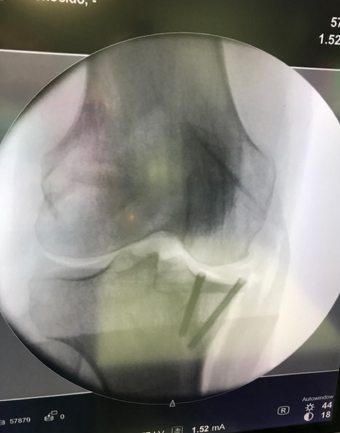

La planificación ha consistido en trasplantar la superficie articular de la meseta tibial interna con el aloinjerto, corregir la deformidad mediante la osteotomia tibial, con un corte en cuña del hueso tibial para realinear la articulación, y fijarla con una placa radiotransparente.

La ventaja de esta indicación es preservar la articulación del paciente y devolverle al mismo su anatomía previa, que estaba desestructurada debido a la fractura inicial, evitando la implantación de una prótesis de rodilla a corto plazo. En la literatura médica, las tasas de supervivencia de estos aloinjertos son del 95% a los cinco años, 80% a los diez años y 65% a los quince años.